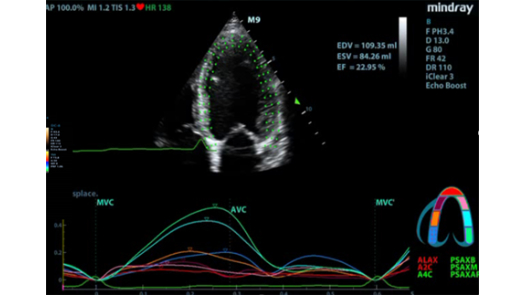

MX7? ??? ZST+ ???? ???? ??? ??? ???? ?? ??? ?? ??? ??? ??? ?? ???? ?? ???? ?????? ?????. ??? ?? ??? ?? 8??? ??? ??? ?? ?? ??? ?? ???? ??? ?????. ?? ?? ? ?? ??? ?? ??? ??? ? ????.